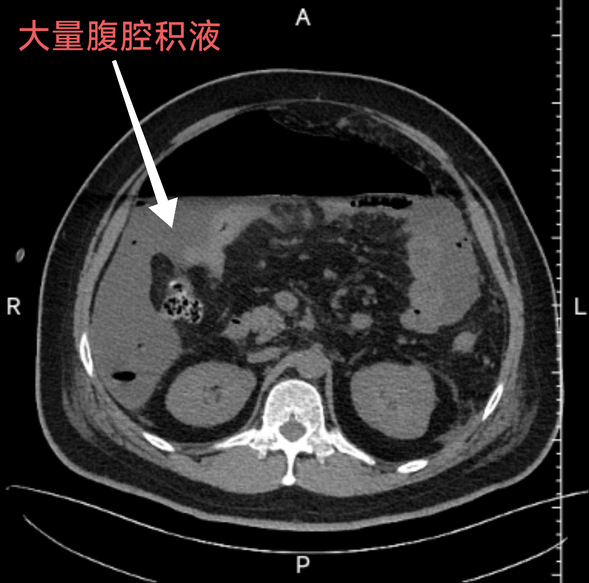

患者因持续性腹部疼痛3天就诊于内蒙古扎兰屯某医院,但因病情复杂、风险极高被建议转诊至具备更高救治能力的医疗机构。家属辗转联系到我院普外三科(肿瘤外科)主任邵学谦,尽管此时正值非急诊班时段,普外三科(肿瘤外科)医护团队仍以高度的责任感迅速响应,第一时间启动危重症抢救流程。该患者全腹CT检查显示:消化道穿孔伴广泛腹腔积液,实验室指标提示贫血、低白蛋白血症、低血容量及全身炎症反应。入院时,患者已出现全腹压痛、反跳痛等急性腹膜炎体征并伴有感染性休克,病情凶险,穿孔部位待排,情况十分危急,需争分夺秒实施手术干预。

患者术前腹部CT

在完善术前检查后,立即决定对患者行急诊手术治疗,术中探查发现,患者腹腔内积聚约4000ml混浊粪水样液体,小肠中段存在直径约1.5cm穿孔及近50cm左右小肠呈炎性改变,肠内容物严重污染腹腔,导致肠管广泛扩张、黏连成团,系膜间血管交错缠绕,手术难度极大。团队需在短时间内完成以下关键操作:1. 彻底清除腹腔污染源:及时引出腹腔内大量积液,精准分离粘连肠管,避免术中二次损伤;2. 手术术式选择:采用“小肠部分切除术+端侧吻合术”重建肠道连续性;3. 腹腔粘连松解术:解除肠梗阻风险,降低术后复发概率;4. 抗休克综合管理:术中同步纠正低血压、电解质紊乱及凝血功能障碍。